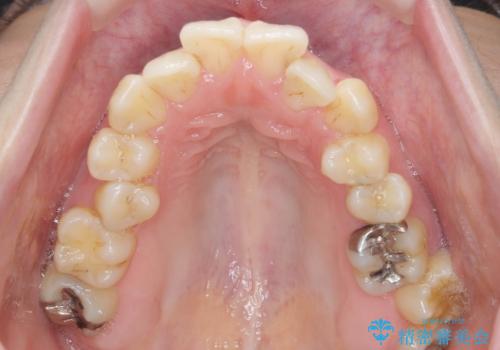

前歯のがたつき すれ違い咬合のマウスピース矯正治療

- 前歯のがたつきや歯の角度、矯正治療を希望され来院されました。

仕事の都合で、ワイヤー矯正を行うことが難しくマウスピース矯正であれば可能、という希望でした。

下顎が前にある咬合関係を可及的に咬合移動で改善し、IPR、下顎3前歯の仕上げで行うマウスピース矯正を計画します。